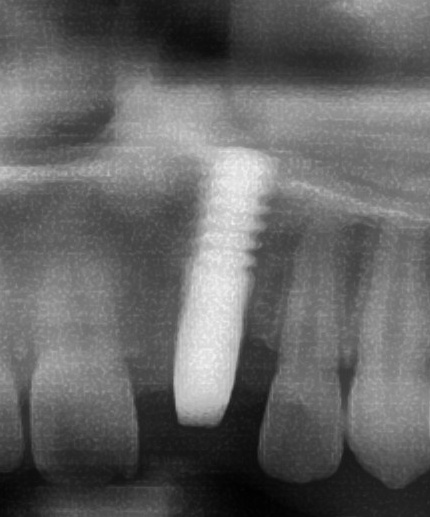

開けた穴に、専用道具を使ってネジを締めるように長さ2センチ程のインプラントを骨に埋め込んでいきます。

しっかりとインプラント埋め込まれた後は、動揺がないか、噛んだ時に当たらないかなどを確認して、最後にパノラマ写真を撮影して今回のオペは終了となりました。